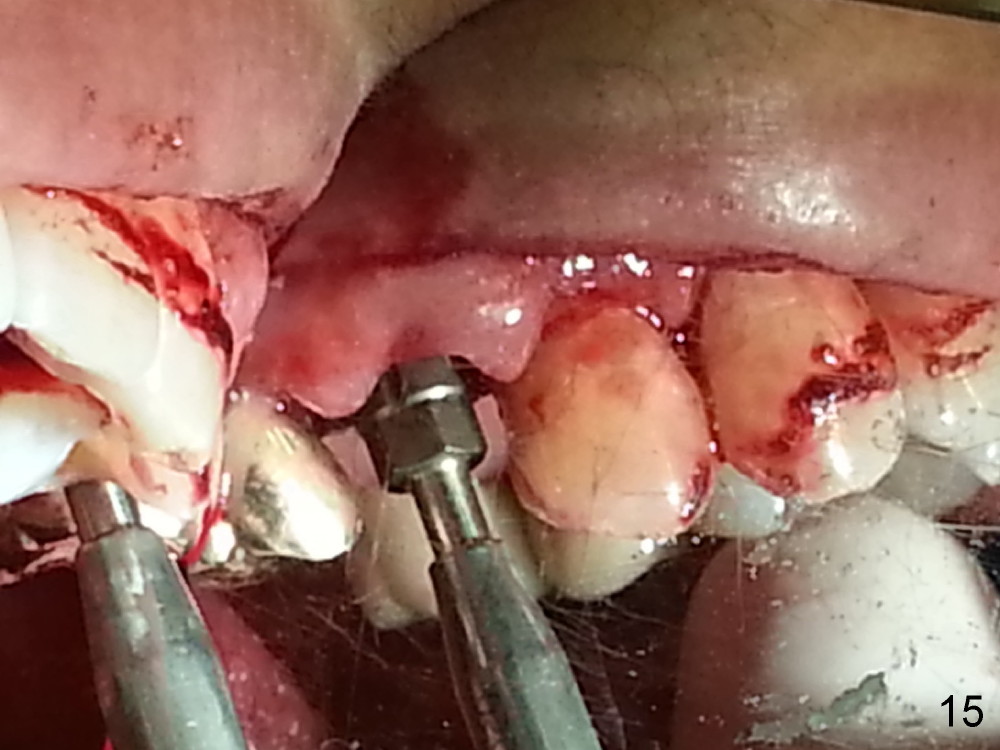

The tooth #13 appears to be affected by periodontits and occlusal trauma (Fig.1*). After using a periotome (Fig.2), the tooth is extracted (Fig.3). The buccal flap is raised (Fig.4). Gingival graft is to be harvested from the site of #15 (Fig.5). The tissue is elevated buccally (Fig.6) and separated (Fig.7). The donor site is covered by a collagen membrane (Fig.8*). A diamond bur is used to induce bleeding from the socket (Fig.9*). Osteotomy is initiated (Fig.10) and enlarged (Fig.11,12). A tapered implant is being placed (Fig.13-15) following internal sinus lift (Fig.16,17). The implant is placed subcrestally, followed by bone graft (Fig.18), soft tissue graft (Fig.19), and suturing (Fig.20 <, Fig.21).